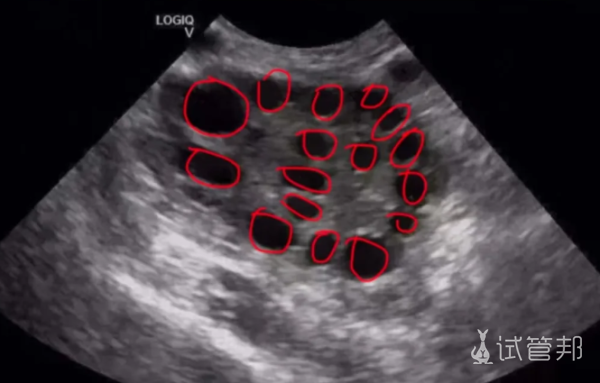

去看多囊卵巢综合征,简直人山人海,感觉多嚢问题现在越来越找上年轻人了。